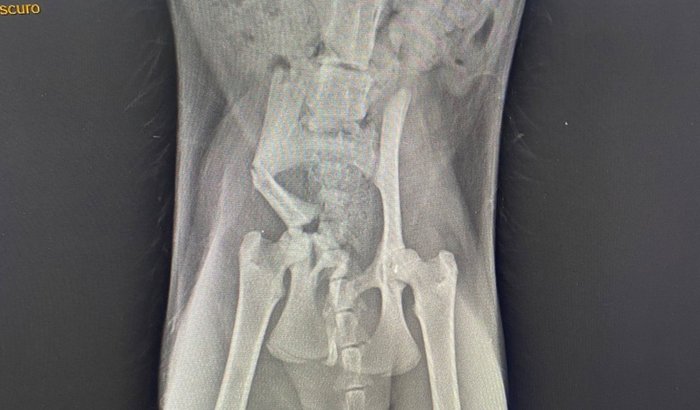

No sábado dia 7/02, Charlene foi encontrada se rastejando e gritando de dor, Charlene tem apenas 4 meses. Foi prestado os primeiros socorros e na segunda dia 9/02, foram realizados ultra e raio x, na ultra consta um coágulo na bexiga, e no raio x mostra uma grande fatura no quadril. Não sabemos oq aconteceu com Charlene, se foi vítima da maldade humana ou se sofreu alguma queda/atropelamento. Mas precisamos urgente realizar a cirurgia para o osso não calcificar errado e depois não ter mais jeito. Ela precisa operar ainda essa semana até dia 14/02, pq não pode passar de 10 dias com osso assim. Precisamos do total de 5.000 mil reais, para a cirurgia q ficou 4500, + pós operatório !